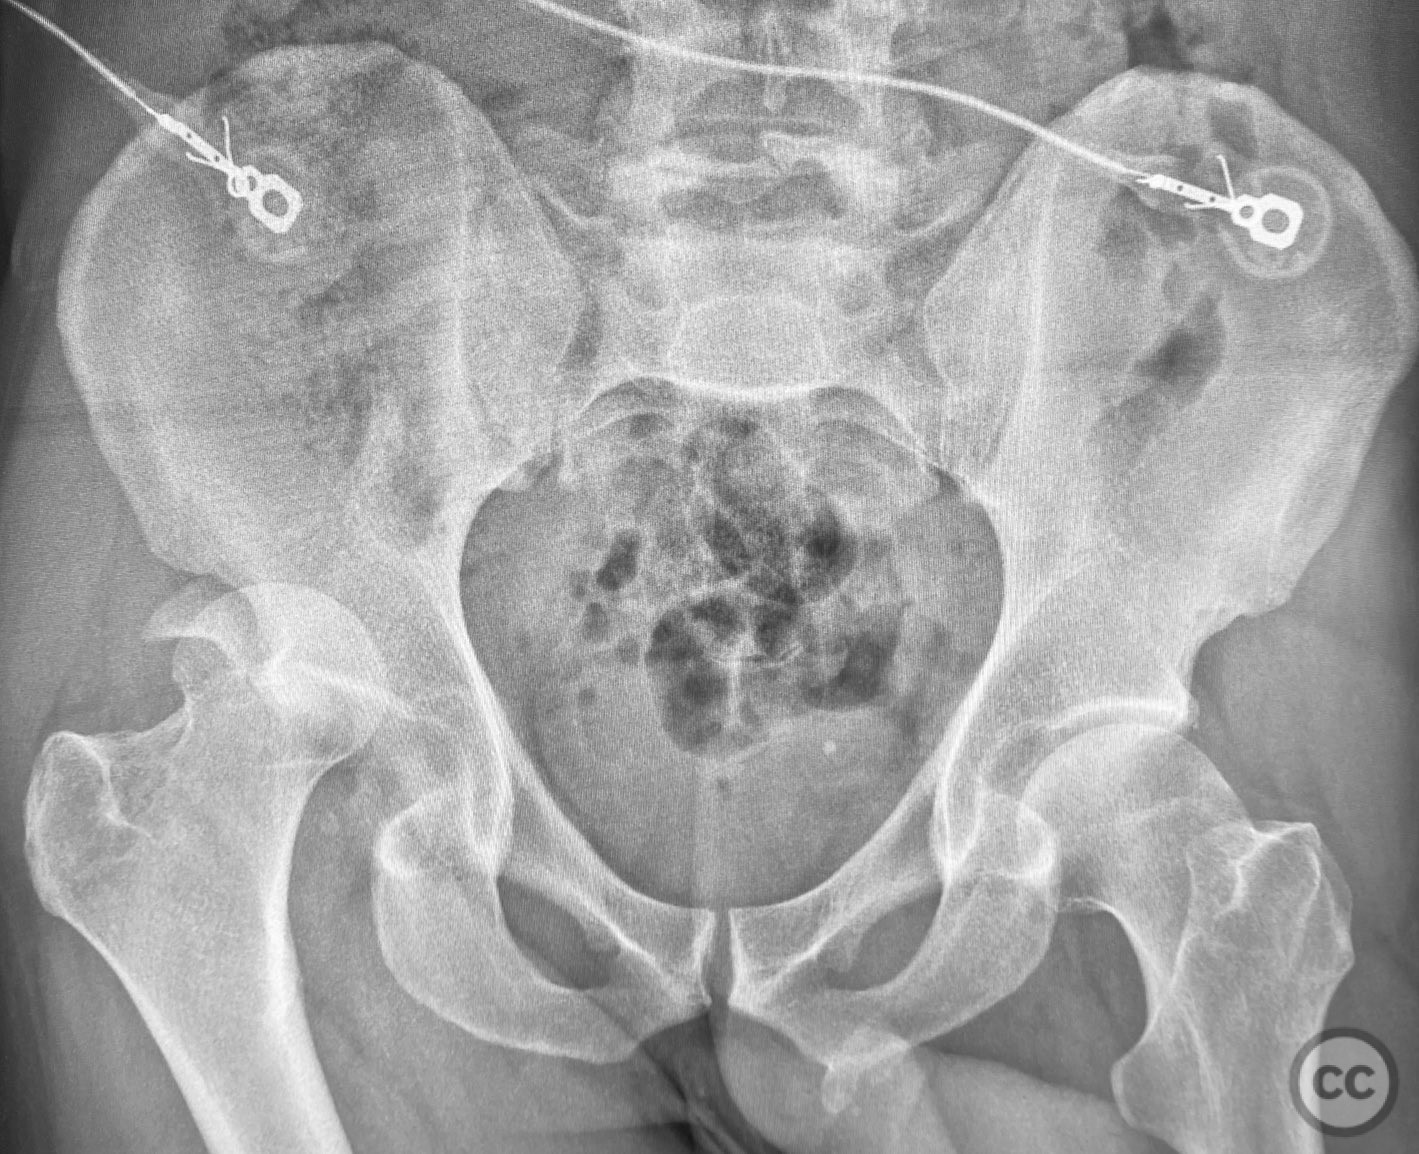

Posterior Wall Acetabular Fracture-Dislo...

Texas, United States

Pelvis - AO/OTA 6x

Complex Acetabular Posterior Wall and Tr...

Posterior Medial Dome Impaction in Assoc...

Posterior Wall and Transverse Acetabular...

Posterior Wall Acetabular Fracture with...

Transverse with Comminuted Posterior Wal...

Unstable Displaced Posterior Column/Post...